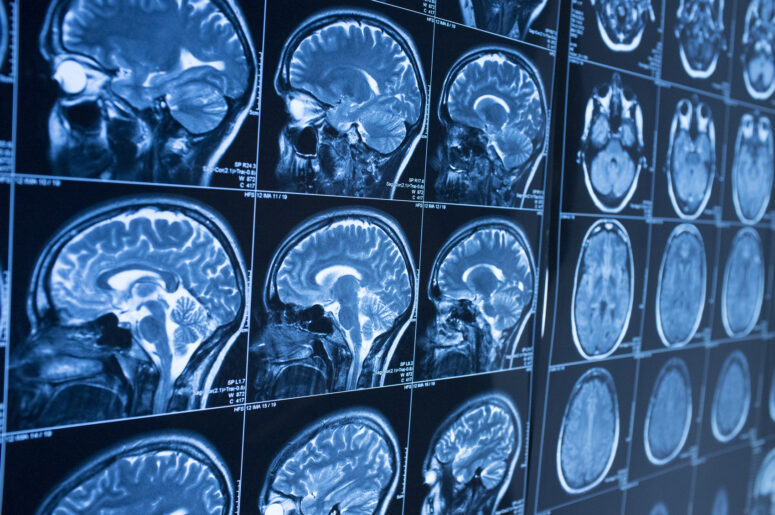

Traditional screening devices used to diagnose moderate to severe brain trauma did not readily show damage that occurred in the white matter of the brain. This mild damage, however, affects key cognitive abilities, including the ability to process language and form memories. Researchers found that diffusion tensor imaging, a form of MRI, can now show physicians where this damage has occurred. Normal white tissue appears structured and orderly on the screening. The damaged areas show darker and pinpoint where the trauma has occurred.